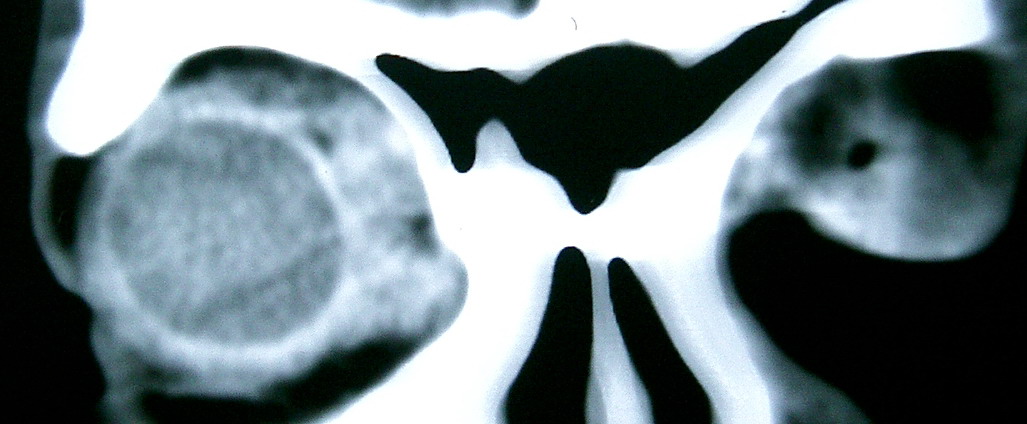

此主题相关图片如下:

按此在新窗口浏览图片

眼眶冠扫,平扫CT:

左眼球内上方可见不规则软组织块影,大小约2.5*1.0CM,与邻近组织分界不清,相邻之内直肌、上直肌增粗,眼环正常,眶壁骨质无破坏,左上颌窦底部可见粘膜增厚,其余副鼻窦未见异常。

IMP:1,左眼眶肿物;2,左上颌窦炎